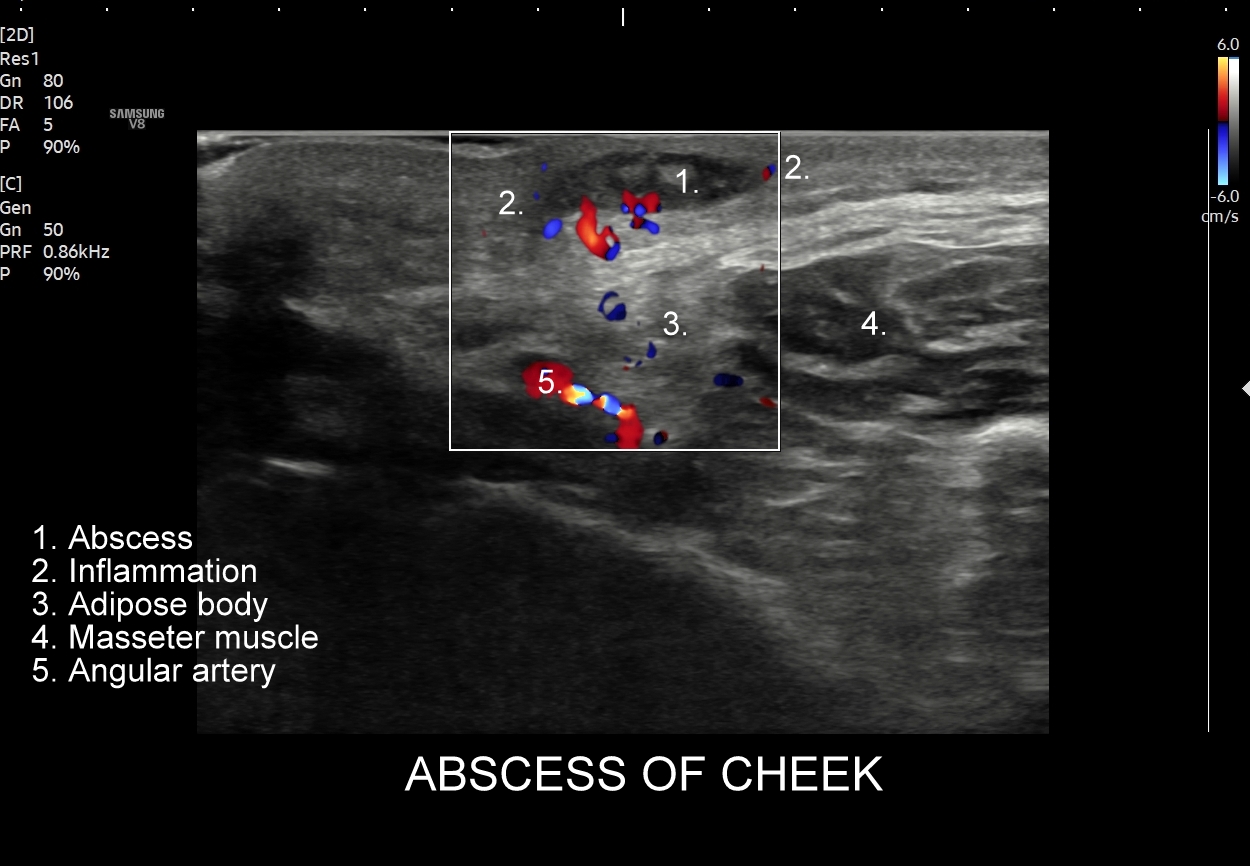

W kontekście powikłań żylnych związanych z trójkątem śmierci należy wspomnieć o zagrażających życiu powikłaniach wstępujących pod postacią zakrzepowego zapalenia zatoki jamistej i głębszych zatok wewnątrzczaszkowych skutkujących obrzękiem mózgu. Poprzez układ żylny oraz tętniczy rozprzestrzeniać mogą się również powikłania infekcyjne, których przykładem są zapalenie opon mózgowo-rdzeniowych i ropień mózgu. Źródłem powikłań infekcyjnych są zapalne stany skóry i tkanki podskórnej w obrębie twarzy oraz trójkąta śmierci, takie jak czyraki i ropnie. Z kolei powikłania zakaźne zstępujące to przede wszystkim infekcyjne zapalenie wsierdzia, zapalenie płuc, czy septyczna zatorowość płucna. Powikłania te związane mogą być również z modnym wśród młodzieży z piercing’iem nosa i warg.

Trójkąt śmierci na twarzy obejmuje również usta. Należy pamiętać, iż są one organami mocno unaczynionymi, co przedstawione jest na załączonych obrazach sonograficznych, a wszelkie infekcje ostre bądź przewlekłe, spontaniczne lub jatrogenne również mogą być przyczyną w/w infekcyjnych powikłań wstępujących oraz zstępujących.